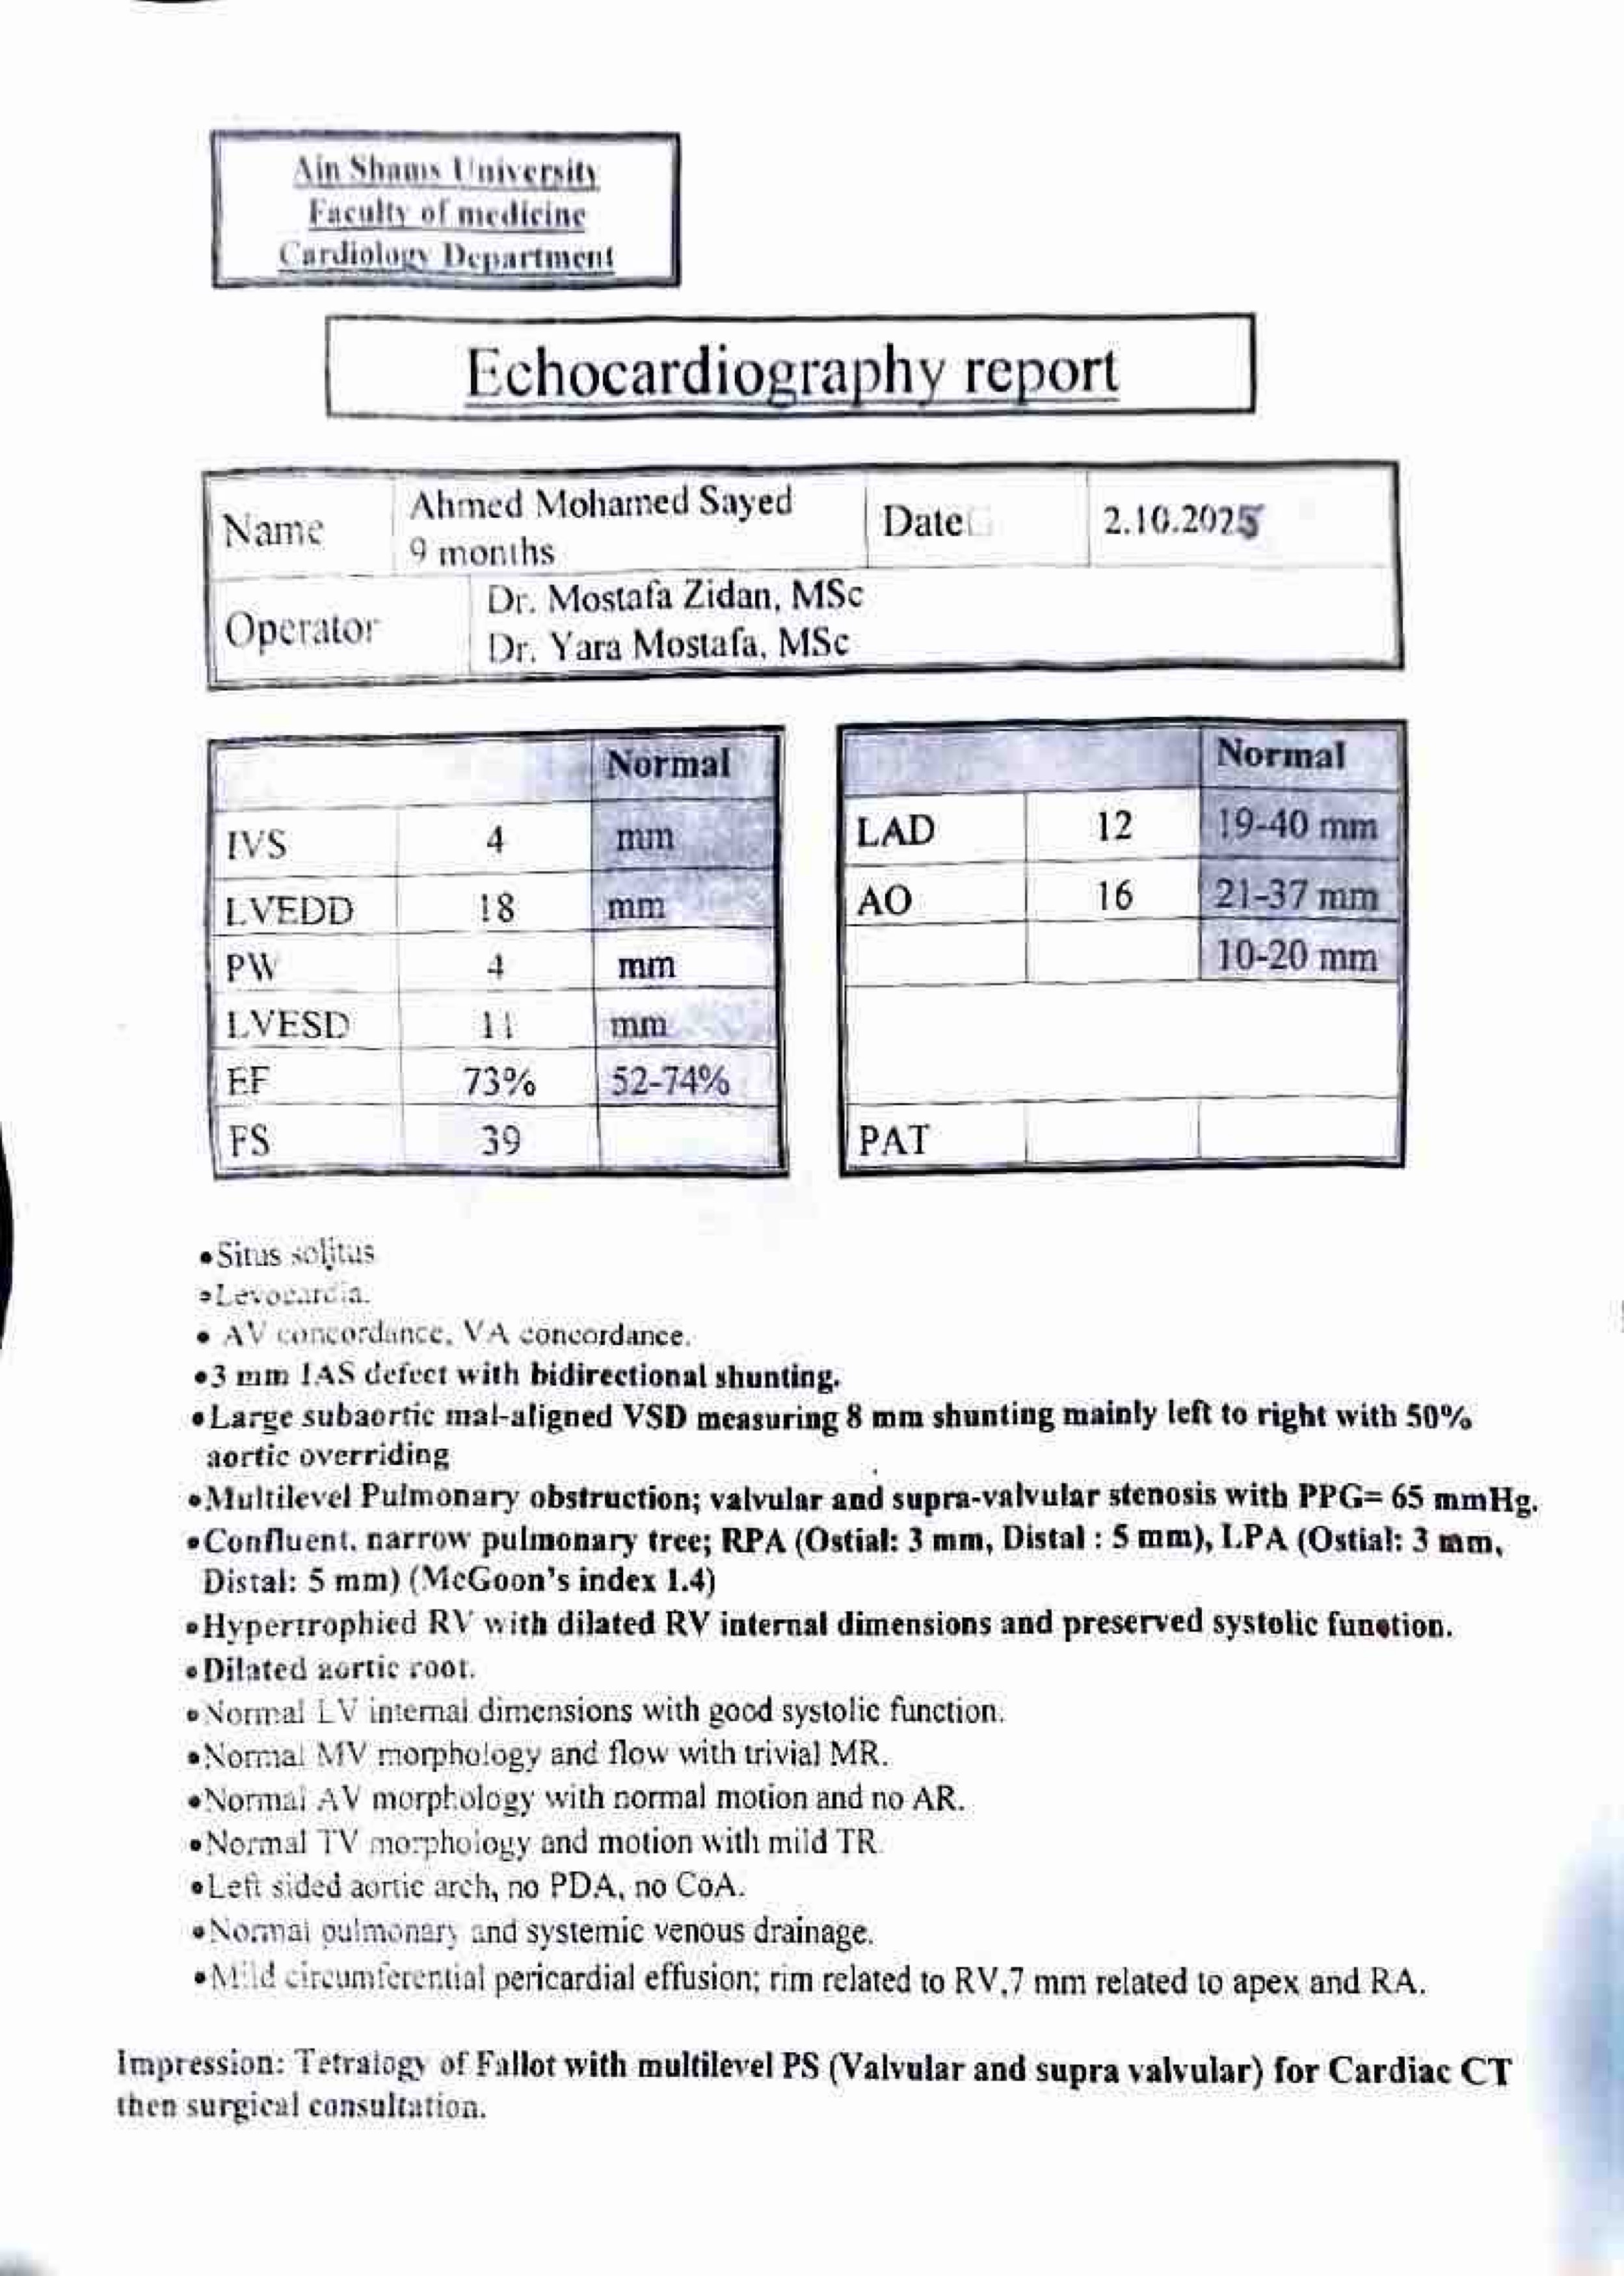

My name is Fahad and I’m looking to help my colleague who is fundraising for her friend in Egypt whose 15 month old child Ahmed is currently suffering from a heart abnormality.

They have unfortunately only been able to pay for the initial diagnosis and have since, not been able to take any further steps to help with Ahmed’s condition. The total cost for the surgery is around E£300,000, which equates to roughly £4300. My colleague has kindly donated some money to help with the cost, but we still require an additional £3000.